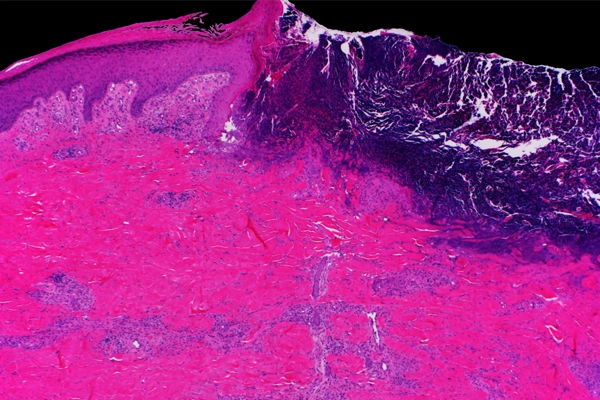

Source : www.rarediseaseadvisor.comMayo Clinic Wound Symposium: The Edges of Evvnt Events